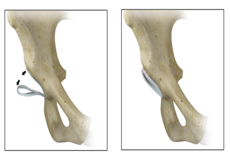

Hip Labral Repair

Labrum is a ring of strong fibrocartilaginous tissue lining around the socket of the hip joint. Labrum serves many functions where it acts as a shock absorber, lubricates the joint, and distributes the pressure equally. It holds the head of the femur in place and prevents the lateral and vertical movement of the femur head within the joint. It also deepens the acetabular cavity and offers stability against femoral head translation.